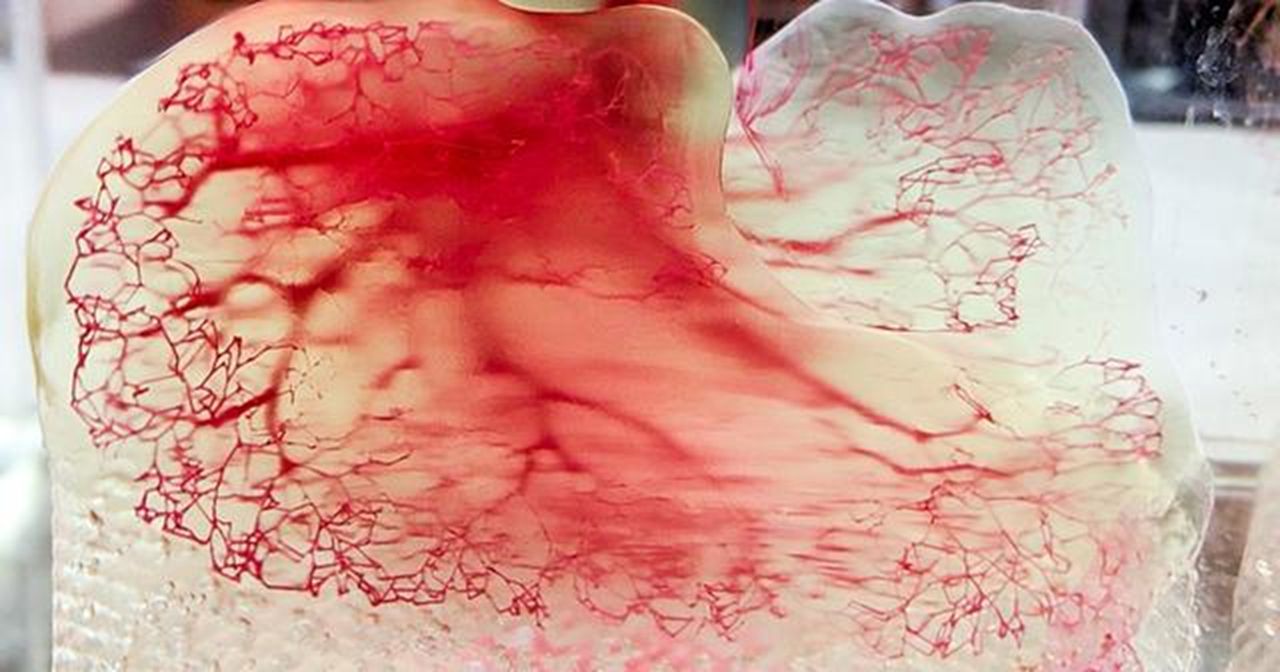

Researchers 3D Print Functional Blood Vessels Using Custom Bioink

Researchers have developed a method of 3D printing blood vessels, and that’s quite important.

New 3D Printed Blood Vessels Could Transform Heart Bypass Operations

Researchers at the University of Edinburgh have developed a method of 3D printing blood vessels.

Ice 3D Printing: A Cool New Approach to Developing Artificial Blood Vessels for Organ Bioprinting

Researchers have developed a unique way to use “ice 3D printing” to help produce artificial human organs.